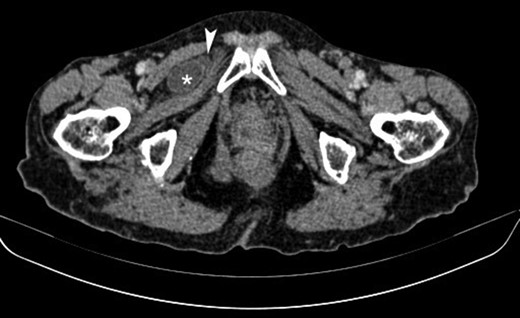

The patient, was admitted to the hospital’s emergency department with a 24-h evolution of diffuse abdominal pain and progressive abdominal distension, associated with persistent vomiting and irradiating pain to the right leg. Patient had a previous history of abdominal surgery including laparoscopic cholecystectomy and repair of umbilical hernia, as well. Physical examination revealed an under-weight female, with distended and tympanitic abdomen, hyperactive bowel sounds with audible rushes associated with vigorous peristalsis, diffuse abdominal pain to deep palpation and no signs of peritoneal irritation or inguino-abdominal hernias. There were neither faeces nor intraluminal mass or blood on the digital rectal examination. Besides, Howship–Romberg sign was negative. The patient maintained her haemodynamic and ventilatory stability. Naso-gastric tube drained ~300 mL of fecaloid fluid. Laboratory exams showed leukocytosis (14 280–70.01% neutrophils) and an increased C-reactive protein level (4.3 mg/L). Upright radiographs demonstrate multiple, short air-fluids levels. Based on the suspicion of an acute bowel obstruction a CT of the abdomen and pelvis was the best applicable solution. The CT scan identified a small intestine segment strangulated through the right obturator foramen and an intestinal distension proximally (Fig. 1). Soon after, the patient underwent an emergent infraumbilical midline laparotomy that confirmed the diagnosis; right obturator hernia with ileal partial wall strangulation (Richter’s type). This was gently released and found to be congested although still viable. Once the bowel loop was released and subjected to warm packs, the colour returned to normal. The obturator hernia defect was roughly 1 × 1 cm2 and this was closed using a single stitch of absorbable polyglactin no. 2 suture (Fig. 2). No other pathology was found. Mass closure of laparotomy wound was with loop polydioxanone (PDS) suture and clips to close the skin. The patient remained stable postoperatively over the course of her hospitalization. She tolerated an oral diet on the second and was discharged on the fourth postoperative day respectively, with an uneventful postoperative recovery.

Axial contrast-enhanced CT image showing a small bowel loop (asterisk) appearing herniated and situated superficially to the obturator externus muscle and deep to the pectineus muscle on the right. Note is made of a small fluid collection adjacent to the herniated loop (arrowhead).